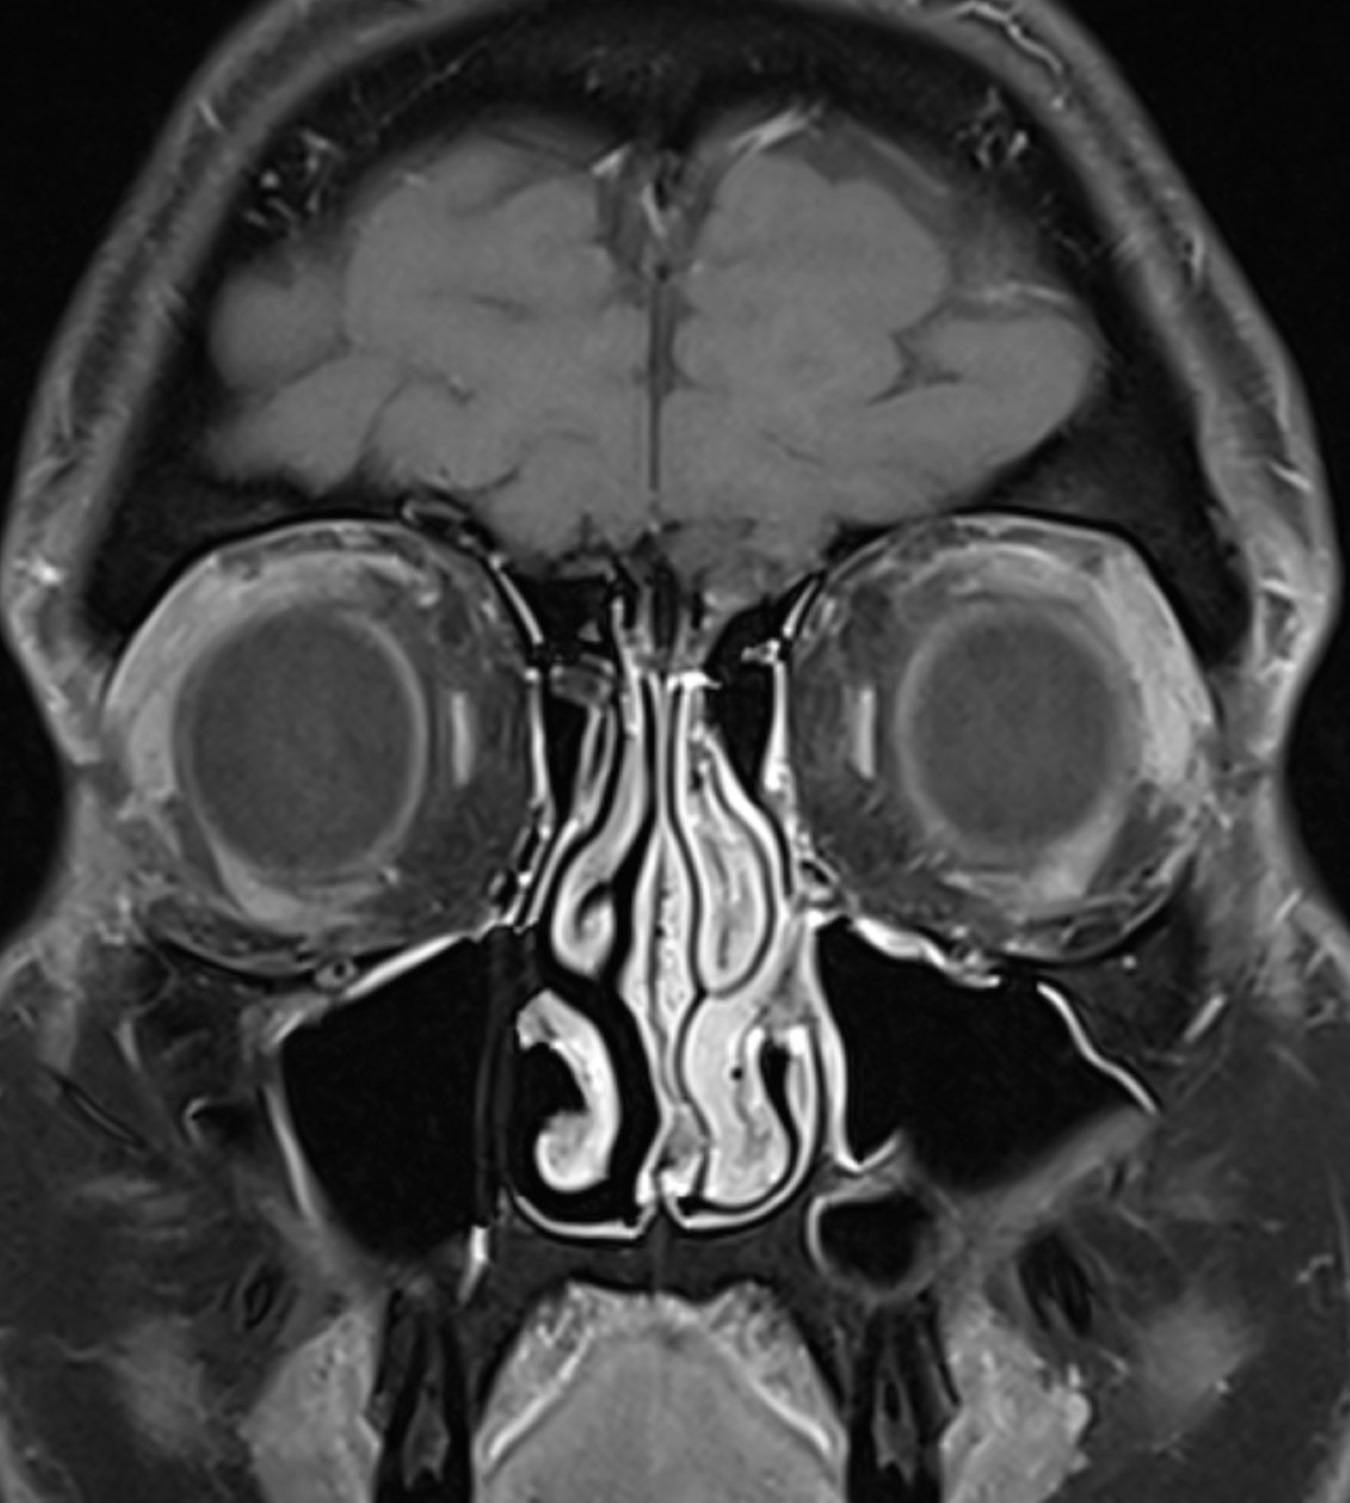

Mrt Gehirn Mit Und Ohne Kontrastmittel Befund Es Gibt Eine 3 5cm Durchmesser Gelappte Masse An from www.istockphoto.com

Mrt Gehirn Mit Und Ohne Kontrastmittel Befund Es Gibt Eine 3 5cm Durchmesser Gelappte Masse An Hirntumor Forum : MRT ohne Kontrastmittel ausreichend? Unterstützen Sie unsere Arbeit für Hirntumorpatienten Die in den USA vorhergesagten angeblichen Hirnschäden habe ich nicht Welche Hirntumore nehmen Kontrastmittel auf? Glioblastome Glioblastome werden durch Hirndruckzeichen, Anfälle oder neurologische Ausfälle, wie z